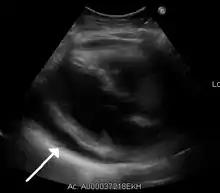

Ultrasounds showing a pericardial effusion in someone with pericarditis

A pericardial effusion as seen on CXR in someone with pericarditis